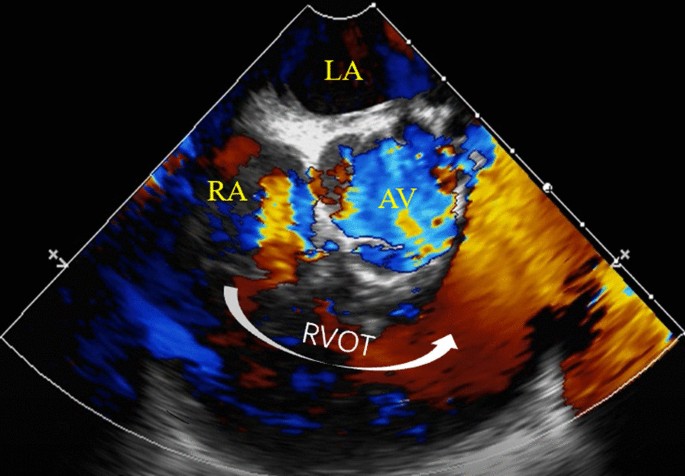

A 44-year-old female was admitted due to abdominal distension and persistent lower limbs edema for over 2 months. Other right-heart-failure-like symptoms caused by systemic congestion were also observed. Transthoracic echocardiogram (TTE) and transesophageal echocardiogram (TEE) found a giant phyllodes mass completely occupies right ventricle (RV, Fig. 1a) and causes right ventricular outflow tract (RVOT) obstruction (Fig. 1b). Contrast-enhanced computed tomography showed an irregular and slightly hypodense shadow (6.2 cm × 3.9 cm) with clear border (Fig. 2) in RV. MRI calculated ejection fraction of RV has sharply decreased compared with that of the left ventricle (24.1% vs. 55.3%) (Additional File 1).

a transthoracic echocardiography before surgery showed a giant tumor (red star) occupied the majority of RV; b Transesophageal echocardiography (ME RV inflow-outflow tract) showed the tumor (red star) in right ventricular caused outflow obstruction. LA left atria, LV left ventricle, RA right atria, RV right ventricle, AAO ascending aorta, AV aortic valve, RVOT right ventricular outflow tract